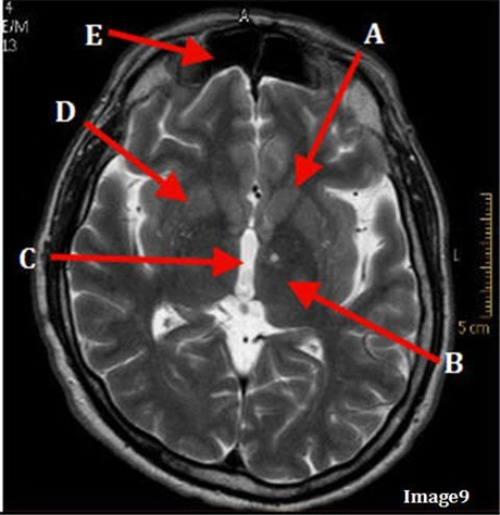

Image 9 is an example of a _____ weighted sequence acquired in the ______ scan plane.

A. T1; Axial

B. T2 FLAIR; sagittal

C. T2; Axial

D. T2; Coronal

Letter E in Image 9 is pointing to:

A. Maxillary sinus

B. Sphenoid sinus

C. Frontal sinus

D. Ethmoid sinus

Letter C in Image 9 is pointing to:

A. Third ventricle

B. Thalamus

C. Lentiform nucleus

D. Caudate nucleus

Letter A in Image 9 is pointing to:

Letter F in Image 13 is pointing to:

A. Grey matter

B. White matter

E. Internal capsule

Letter D in Image 9 is pointing to:

Letter B in Image 9 is pointing to: